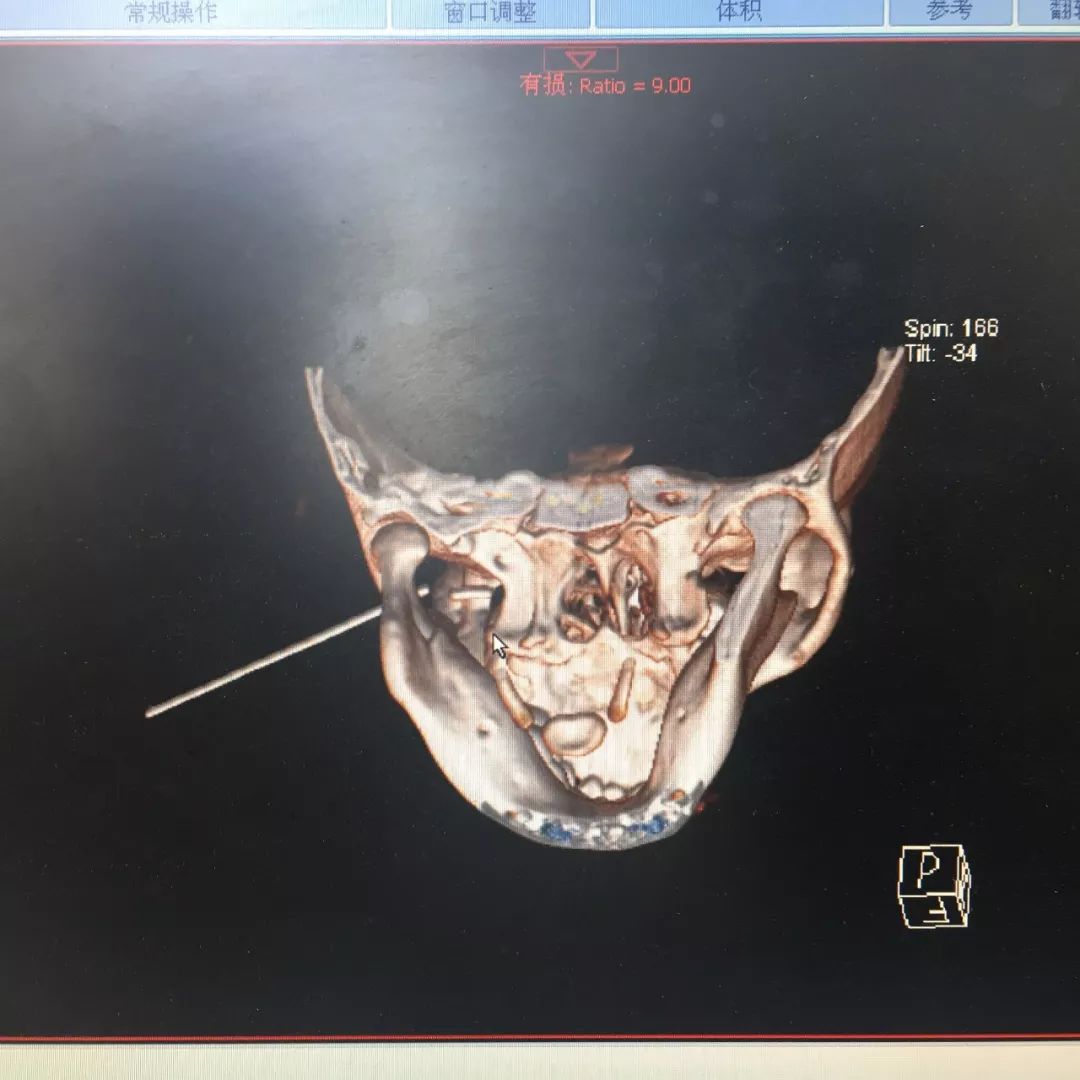

CT显示,铅笔从左颧弓下方斜向上刺入面部,深达4厘米。幸运的是,铅笔没有伤到小雨重要的神经和血管。经医院的紧急手术,一个多小时后,医生顺利将铅笔取出并缝合伤口。

(上图为一8岁男孩被铅笔插入脸部)